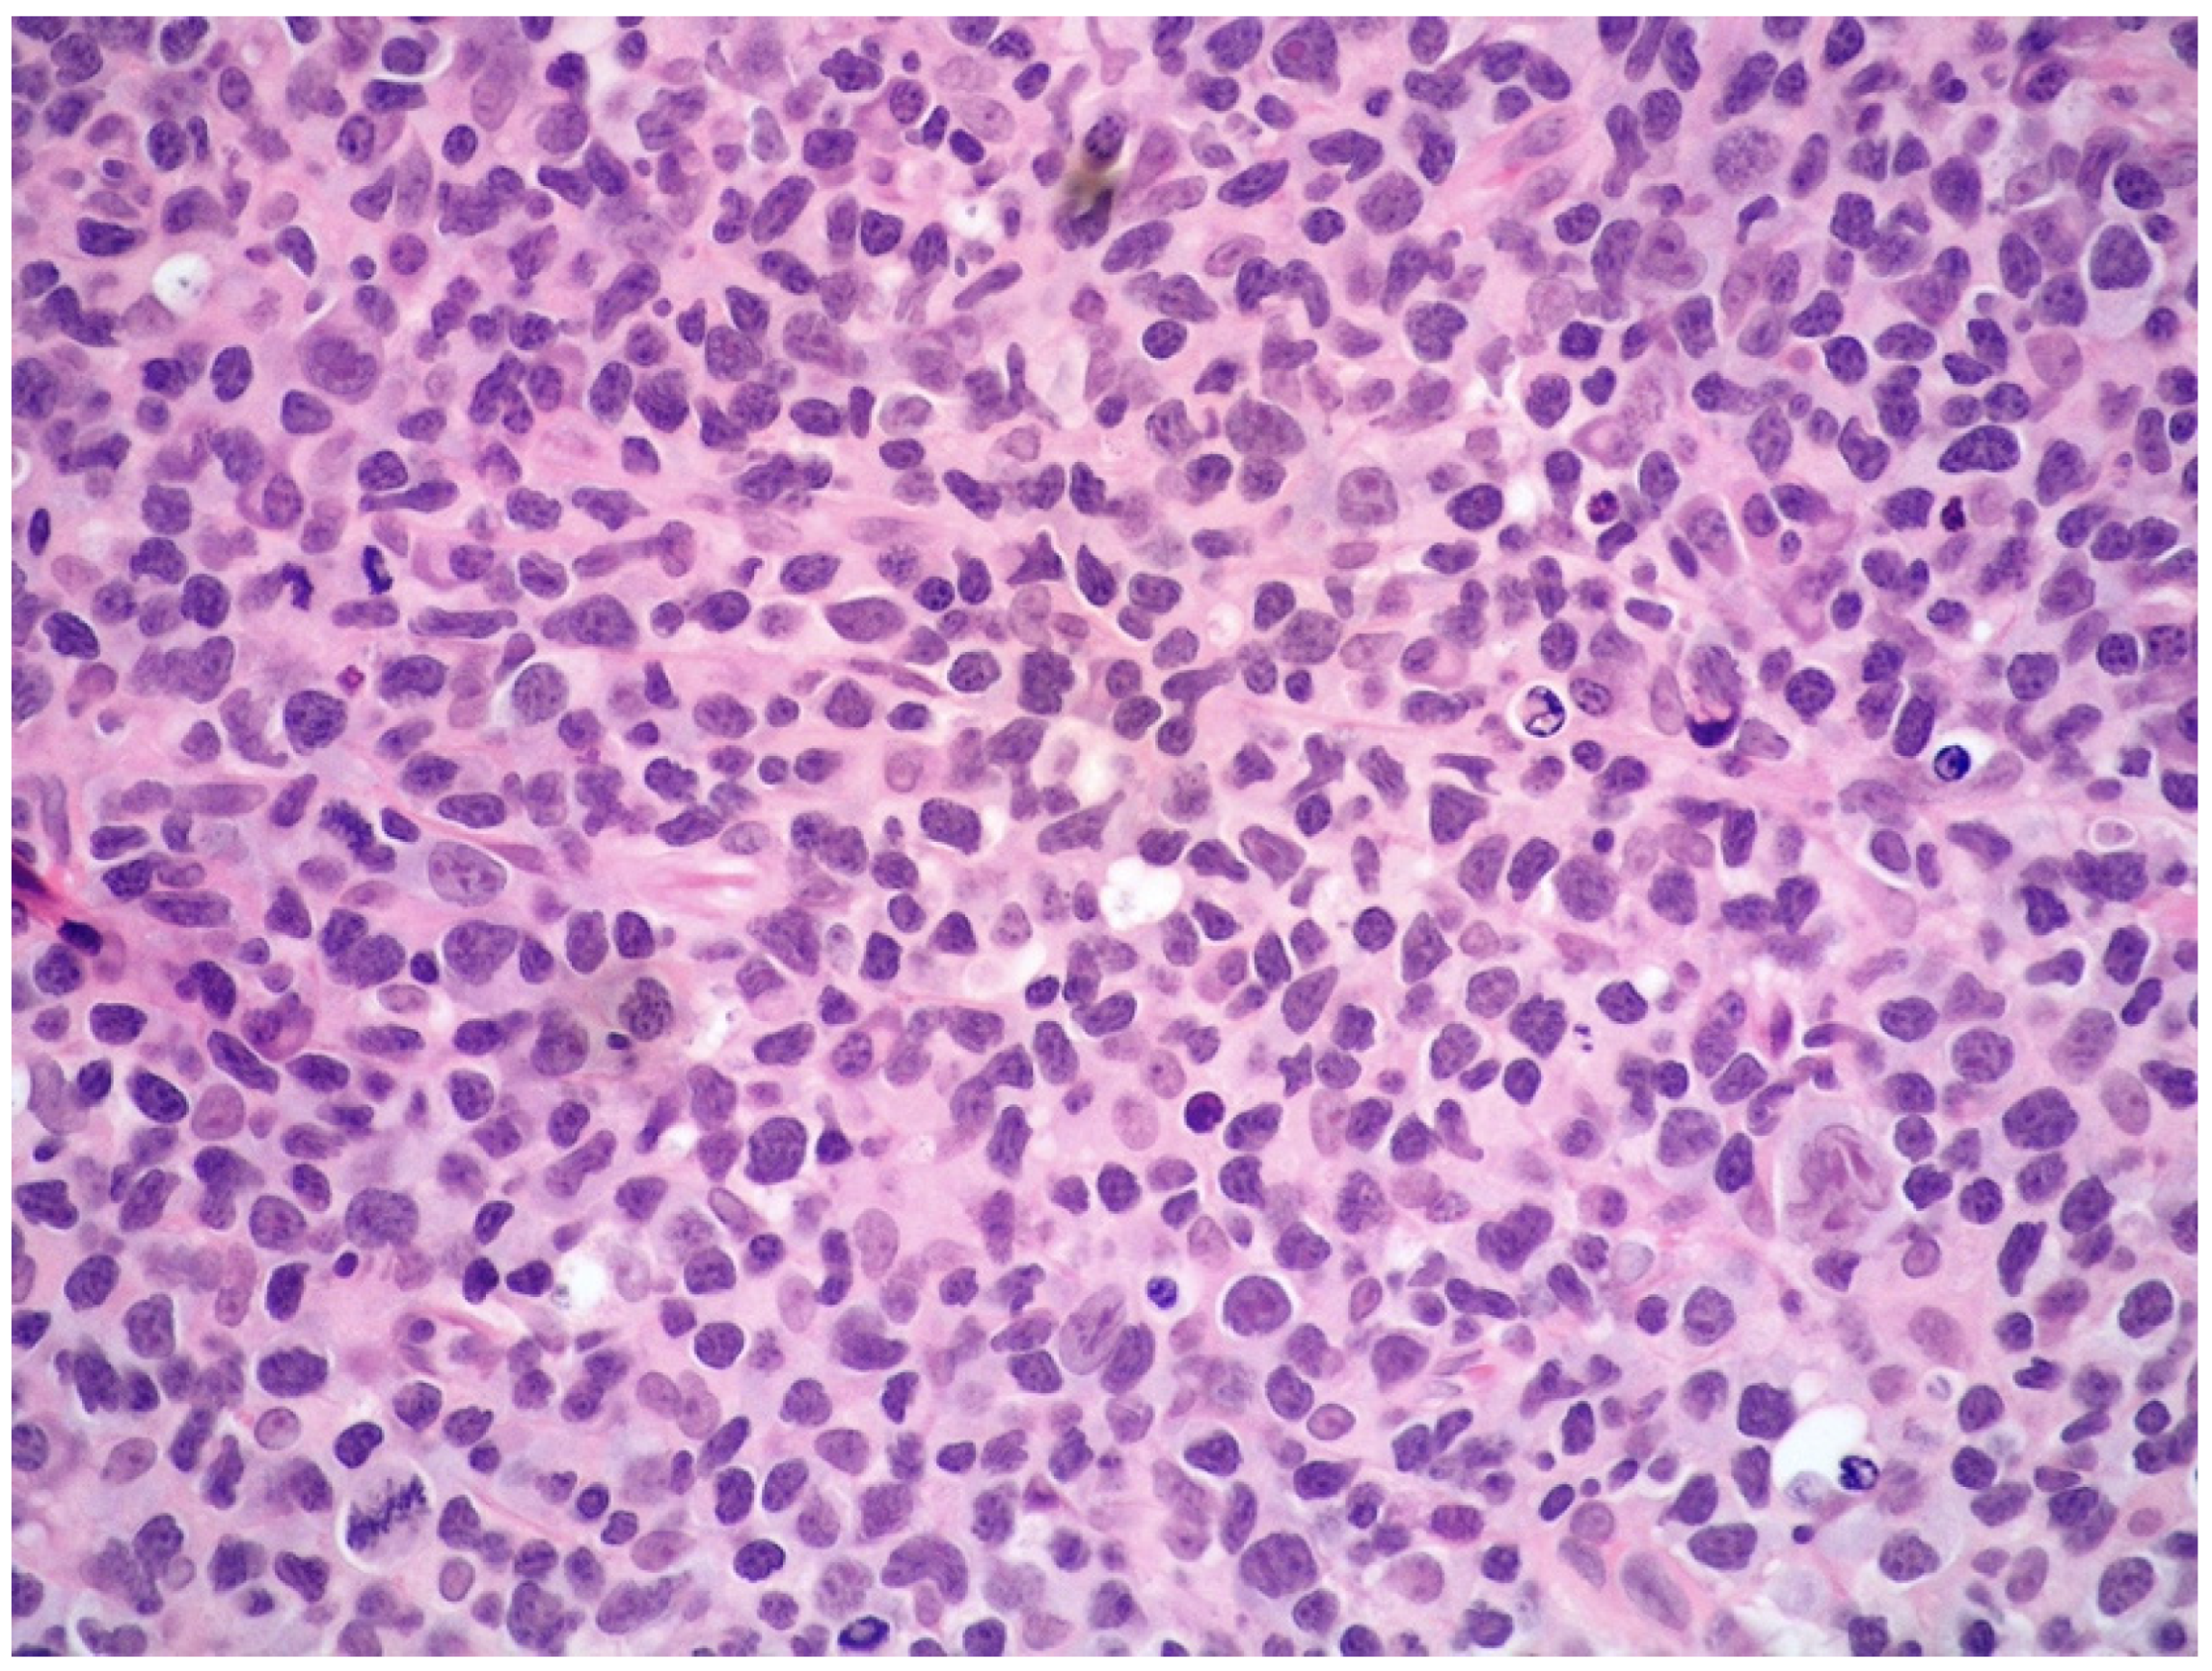

Histologically, the tumor cells are usually discohesive, pleomorphic, and large-sized, with scant cytoplasm and irregular, enlarged nuclei showing hyperchromatic nucleoli; the cells grow inside the lumina of small- to medium-sized vessels without forming a mass (Figure 1 and Figure 2).

The neoplastic elements are rather polymorphic and variable in size, although small- to medium-sized cells with scarce and clear cytoplasm, irregular nucleus, granular chromatin, and inconspicuous nucleolus are generally prevalent. Large-sized lymphoid cells may be present. Mitotic figures are frequent. (Figure 6).

Figure 6. High-power view showing a diffuse and polymorphic proliferation of atypical, medium- to large-sized lymphoid cells (hematoxylin and eosin, 200× magnification, previously unpublished, original image from S.A.).